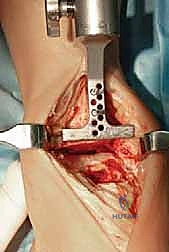

3. إزالة الأسطح التالفة (تحضير العظام)

باستخدام أدوات جراحية دقيقة وموجهات خاصة، يتم إزالة الغضاريف التالفة وجزء رقيق جداً من العظام المريضة من نهايتي عظمة الظنبوب وعظمة الكاحل (Talus). يتم تشكيل العظام بدقة لتتطابق تماماً مع شكل أجزاء المفصل الصناعي.

5. إغلاق الجرح والجبيرة

بعد التأكد من استقرار المفصل الجديد ومدى حركته الممتاز، يقوم د. هطيف بإغلاق الشق الجراحي باستخدام خيوط تجميلية دقيقة لتقليل الندبات. يتم وضع الكاحل في جبيرة أو حذاء طبي خاص لحمايته خلال الأسابيع الأولى من التعافي.